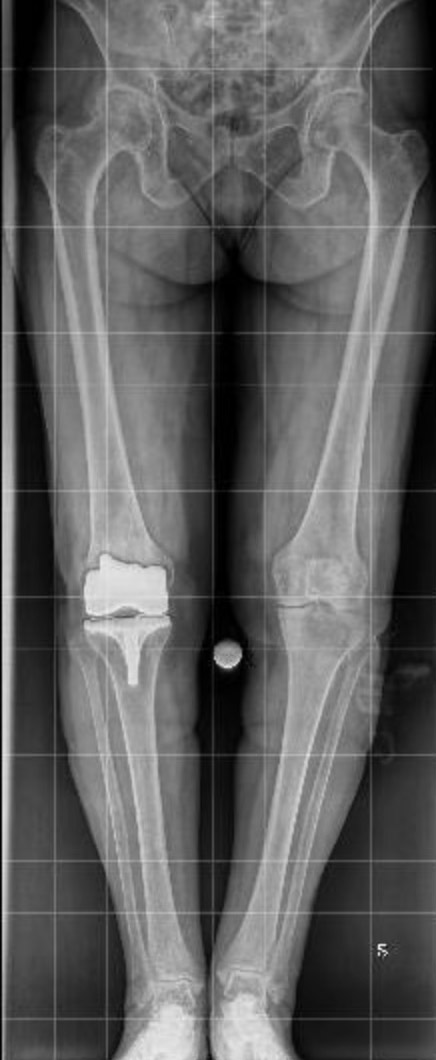

- Teleradiografia degli arti inferiori in carico: Esame essenziale per valutare l’asse di carico e l’allineamento articolare.

- Protesi totale di ginocchio: Riservata ai casi di artrosi avanzata con compromissione diffusa dell’articolazione. Questo intervento mira a ripristinare la funzionalità articolare, ridurre il dolore e migliorare la qualità di vita del paziente.

Questi studi hanno dimostrato come l’utilizzo della robotica consenta una maggiore precisione nell’allineamento degli impianti protesici, sia monocompartimentali che totali, ottimizzando il bilanciamento dei tessuti molli e preservando il più possibile le strutture anatomiche del ginocchio.